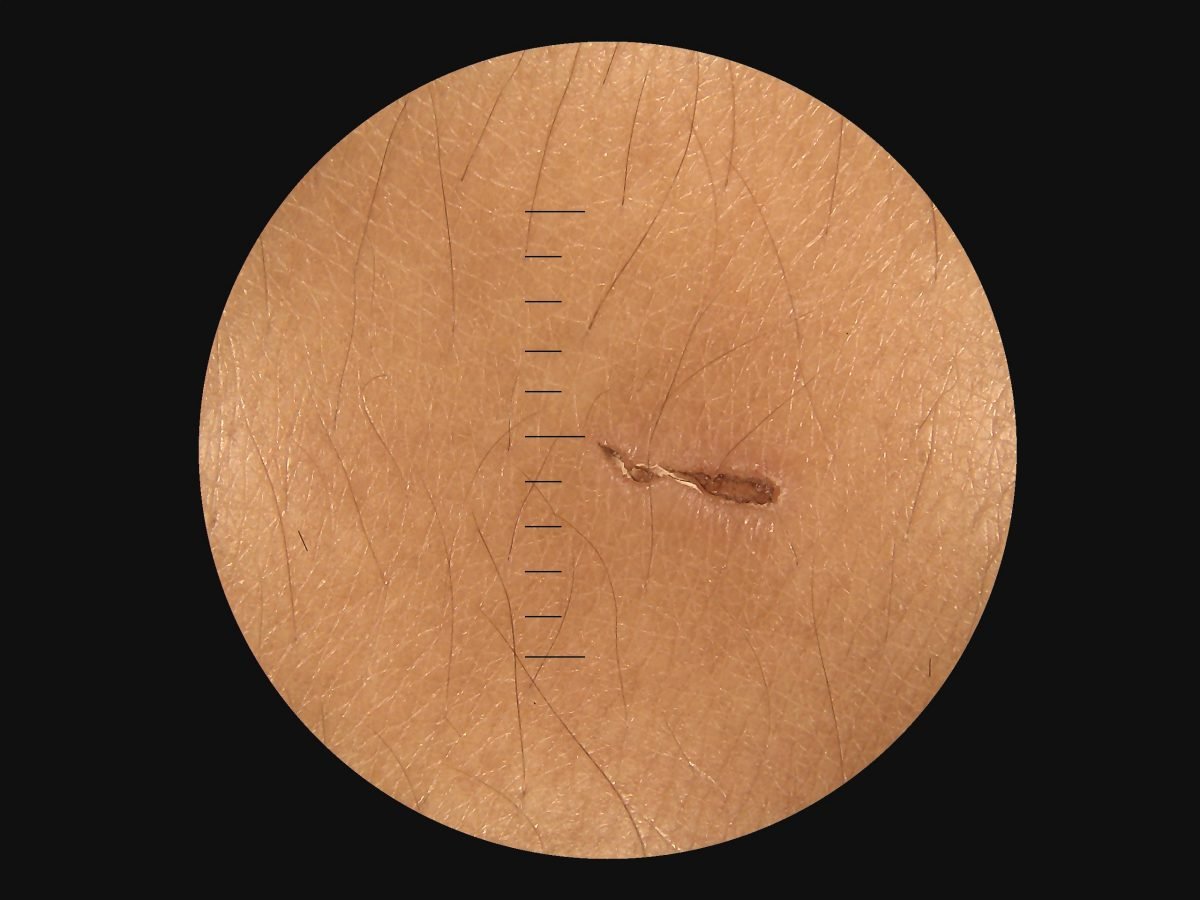

- Provide high definition clinical image

- Portable and hand held application in disease screen

- Multi functional diagnosis in ophthalmology , ENT . Dermatology and general practice.

Image Gallery

Through the scope